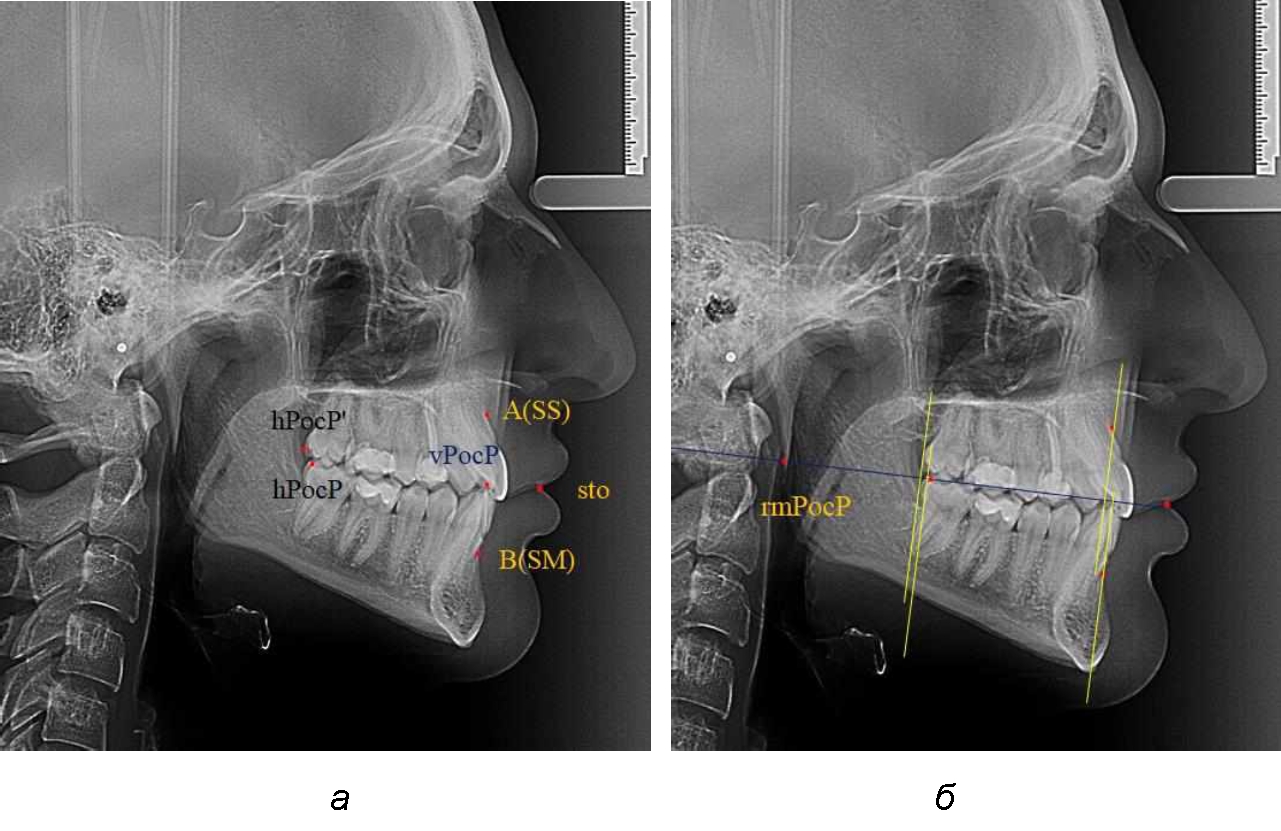

На рентенограммах с признаками дистальной окклюзии Wits-число имело положительные значения. Дистальная точка нижнего моляра была расположена позади верхней дистальной точки окклюзии второго моляра. Относительно равными, так же как и при анализе снимков с мезиальной окклюзией, считались показатели альвеолярно-дентальных размеров, при которых разница не превышала 1,5 мм. Тем не менее расстояние «rmРOcP-A(SS)» превышало расстояние «rmРOcP-B(SM)» в среднем по группе на (5,29 ± 1,47) мм (рис. 4).

Рис. 4. Положение апикальных точек и челюстей при дистальной окклюзии с равными (а) и разными (б) альвеолярно-дентальными размерами зубочелюстных дуг

В тех случаях, когда при дистальной окклюзии альвеолярно-дентальные размеры были различными, размер нижней челюсти превышал аналогичный параметр верхней челюсти, в среднем на (3,62 ± 1,12) мм.